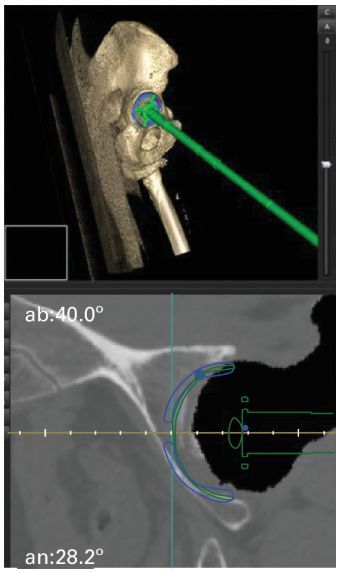

North India’s first navigation system for minimally invasive hip replacement is here at Sarvodaya Hospital. More precision. Less pain. Faster recovery. 📞 1800 313 1414 #sarvodayahealthcare #hipreplacement #minimallyinvasivesurgery #orthopediccare #hippainrelief

Sarvodaya_Care's tweet image. North India’s first navigation system for minimally invasive hip replacement is here at Sarvodaya Hospital.

More precision. Less pain. Faster recovery.